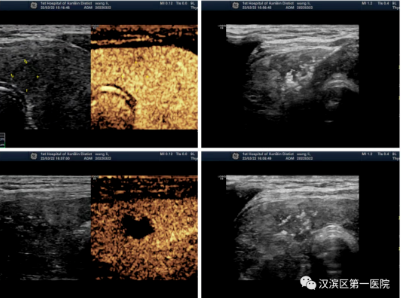

甲状腺结节消融术中即刻超声造影

上图分别为甲状腺结节消融术前造影、消融术中、消融术后即刻造影、消融术后常规超声

针对广大甲状腺结节患者,可实施超声引导下甲状腺实性结节射频消融术,让患者最大程度上获益。具体步骤:术前进行超声造影检查,明确结节的位置及大小,术后即刻行超声造影评估,明确消融区范围完全覆盖结节,证实该结节完全消融。通常在消融术后一个月,复查超声造影对局部疗效再评估。

超声造影检查已越来越多地应用于临床各类肿瘤的诊断,以及各种外科手术或微创介入治疗过程中的监测和疗效评估,尤其在肝胆胰等疾病的诊疗中发挥着重要作用。目前,我科与肝胆腺体外科合作,已经成熟开展多例超声引导下肝肿瘤射频消融术和甲状腺结节射频消融术,给多名患者带来了福音。